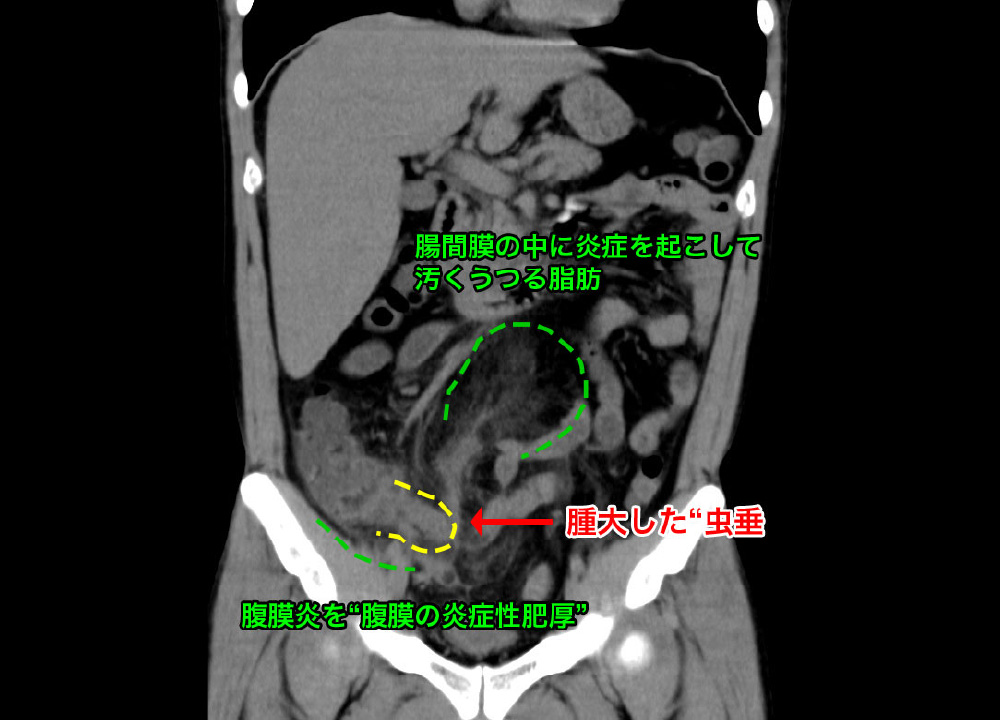

急性虫垂炎

腹痛と血尿を訴えて受診。

虫垂が破れて、周囲に うみ をためています。炎症の波及で、膀胱へ波及→血尿が出ていました。

急性虫垂炎 急性虫垂炎 急性虫垂炎

急性虫垂炎 腫大した 虫垂 が造影されています。別症例です。